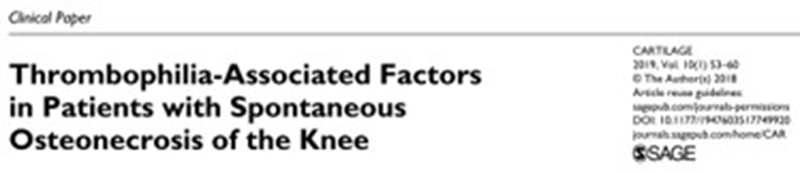

一项研究表明,52%(13/25)患者中血栓形成相关因子水平异常,其中以高纤维蛋白原最为突出)。

另一项结果中,32例患者的因子ⅤLeiden和凝血酶原20210A基因发生率更高。这两种基因突变会引起凝血功能异常而更容易形成血栓,造成膝关节软骨下骨循环障碍而出现坏死。

2014年的一项研究中,在6名Ⅱ期SONK患者均患有血栓形成倾向,其中4名同时患有低纤维蛋白溶解,接受依诺肝素治疗的易血栓性低纤溶性患者没有出现塌陷或进展为严重的骨关节炎,并且大多数患者的疼痛得到缓解并恢复了全部功能。